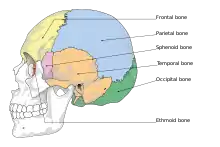

They typically require a significant degree of trauma to occur.[1] The break is of at least one of the following bones: temporal bone, occipital bone, sphenoid bone, frontal bone, or ethmoid bone.[1] They are divided into anterior fossa, middle fossa, and posterior fossa fractures.[1] Facial fractures often also occur.[1] Diagnosis is typically by CT scan.[1]

Basilar skull fractures include breaks in the posterior skull base or anterior skull base. The former involve the occipital bone, temporal bone, and portions of the sphenoid bone; the latter, superior portions of the sphenoid and ethmoid bones. The temporal bone fracture is encountered in 75% of all basilar skull fractures and may be longitudinal, transverse or mixed, depending on the course of the fracture line in relation to the longitudinal axis of the pyramid.[6]